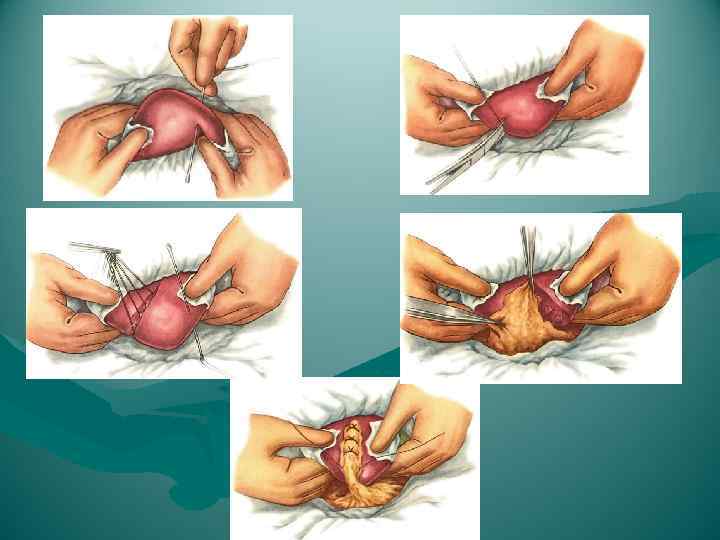

РЕЗЕКЦИЯ ПЕЧЕНИ Основная радикальная операция при ранениях и опухолях печени По технике выполнения Типичные (анатомические) - европейский способ - с предварительной перевязкой кровеносных сосудов и желчного протока удаляемого участка печени Преимущество - хороший гемостаз Недостаток - большой объем удаляемого участка: независимо от очага поражения удаляется сегмент или доля Виды типичной резекции печени: - гемигепатэктомия (право - и левосторонняя) - лобэктомия (удаление сектора) • правосторонняя латеральная • правосторонняя парамедианная • левосторонняя парамедианная - сегментэктомия и субсегментэктомия (изолированное удаление первых 6 сегментов; VII и VIII сегменты отдельно не удаляются, т. к. нарушается отток крови от V и VI сегментов).

РЕЗЕКЦИЯ ПЕЧЕНИ Основная радикальная операция при ранениях и опухолях печени По технике выполнения Типичные (анатомические) - европейский способ - с предварительной перевязкой кровеносных сосудов и желчного протока удаляемого участка печени Преимущество - хороший гемостаз Недостаток - большой объем удаляемого участка: независимо от очага поражения удаляется сегмент или доля Виды типичной резекции печени: - гемигепатэктомия (право - и левосторонняя) - лобэктомия (удаление сектора) • правосторонняя латеральная • правосторонняя парамедианная • левосторонняя парамедианная - сегментэктомия и субсегментэктомия (изолированное удаление первых 6 сегментов; VII и VIII сегменты отдельно не удаляются, т. к. нарушается отток крови от V и VI сегментов).

ЭТАПЫ ТИПИЧНОЙ (АНАТОМИЧЕСКОЙ) РЕЗЕКЦИИ ПЕЧЕНИ 1. Лапаротомия 2. Выделение и перевязка в портальных воротах печени ветвей a. hepatica propria, v. portae, ductus hepaticus (глиссонова ножка) удаляемой части печени 3. Рассечение паренхимы печени по междолевым щелям, ограничивающим резецируемую часть 4. Выделение и перевязка печеночных вен в кавальных воротах печени 5. Удаление резецируемой части с перитонизацией раневой поверхности печени (большой сальник, круглая или серповидная связка, синтетические ткани) 6. Зашивание раны брюшной стенки

ЭТАПЫ ТИПИЧНОЙ (АНАТОМИЧЕСКОЙ) РЕЗЕКЦИИ ПЕЧЕНИ 1. Лапаротомия 2. Выделение и перевязка в портальных воротах печени ветвей a. hepatica propria, v. portae, ductus hepaticus (глиссонова ножка) удаляемой части печени 3. Рассечение паренхимы печени по междолевым щелям, ограничивающим резецируемую часть 4. Выделение и перевязка печеночных вен в кавальных воротах печени 5. Удаление резецируемой части с перитонизацией раневой поверхности печени (большой сальник, круглая или серповидная связка, синтетические ткани) 6. Зашивание раны брюшной стенки

РЕЗЕКЦИЯ ПЕЧЕНИ Атипичные резекции - восточный способ - удаление части органа в пределах здоровых тканей с постепенным, по ходу намеченного пересечения печени, раздавливанием пальцами паренхимы и перевязыванием пальпаторно обнаруженных сосудистых и желчных образований: - краевая - клиновидная - поперечная Основной момент операции - шов печени Преимущество - более экономна с точки зрения количества удаляемой ткани - простота и быстрота Недостаток - возможность опасных неуправляемых кровотечений - возможность некрозов остающихся здоровых участков печени из-за перевязки их сосудов и желчных протоков

РЕЗЕКЦИЯ ПЕЧЕНИ Атипичные резекции - восточный способ - удаление части органа в пределах здоровых тканей с постепенным, по ходу намеченного пересечения печени, раздавливанием пальцами паренхимы и перевязыванием пальпаторно обнаруженных сосудистых и желчных образований: - краевая - клиновидная - поперечная Основной момент операции - шов печени Преимущество - более экономна с точки зрения количества удаляемой ткани - простота и быстрота Недостаток - возможность опасных неуправляемых кровотечений - возможность некрозов остающихся здоровых участков печени из-за перевязки их сосудов и желчных протоков

Мобилизация левой доли

Мобилизация левой доли

Раздавливание печени

Раздавливание печени

Резекция доли печени

Резекция доли печени